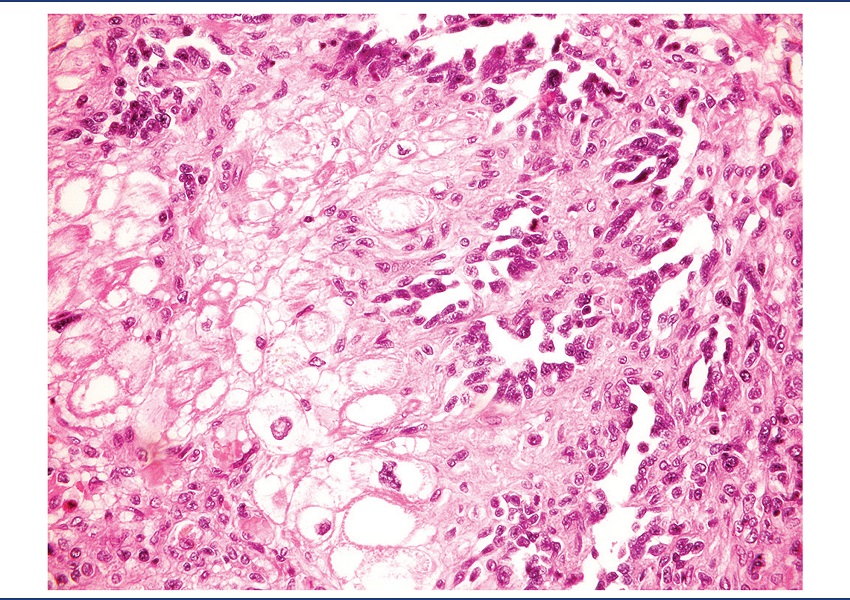

On pathological examination, the specimen was received fragmented, measuring 9.2 × 7 × 4 cm. There was a brownish nodule with hemorrhagic areas, measuring 4 cm in diameter, apparently infiltrating the cardiac wall (Figure 2). Microscopically, it was identified as a mesenchymal neoplasm, characterized by the proliferation of atypical endothelial cells with irregular nuclei, sometimes round sometimes spindle, without evident nucleolus, forming vascular spaces, papillae, and solid areas. Mitoses were frequent and necrosis was not observed. The lesion permeated cardiomyocytes, which presented clear cytoplasm and hypertrophic nucleus (Figures 3 to 7). There was infiltration of the visceral pericardium. The diagnosis was primary cardiac angiosarcoma.

HE: hematoxylin and eosin.

Histology can reveal different aspects, depending on the degree of differentiation. Well-differentiated areas are made by atypical pleomorphic endothelial cells, which form papillary structures or vascular channels. The poorly differentiated areas are formed by spindle anaplastic cells in solid pattern(7). The tumor presented both well-differentiated and poorly differentiated areas.